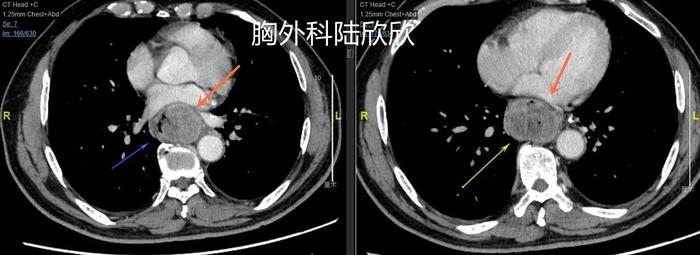

上图,心脏和脊柱间有巨大的软组织影,心脏被挤压变形。

上图,脊柱前扩张的近端食管,扩张明显,内部有食物和粘液。肿瘤近端的食管明显扩张增粗。对于消化道肿瘤来说,只要是肿瘤引起的梗阻比较厉害,肿瘤近端的消化道管腔扩张就比较厉害。

上图,肿瘤周围的淋巴结,术后病理证实为转移淋巴结。只有这一个淋巴结发生转移。